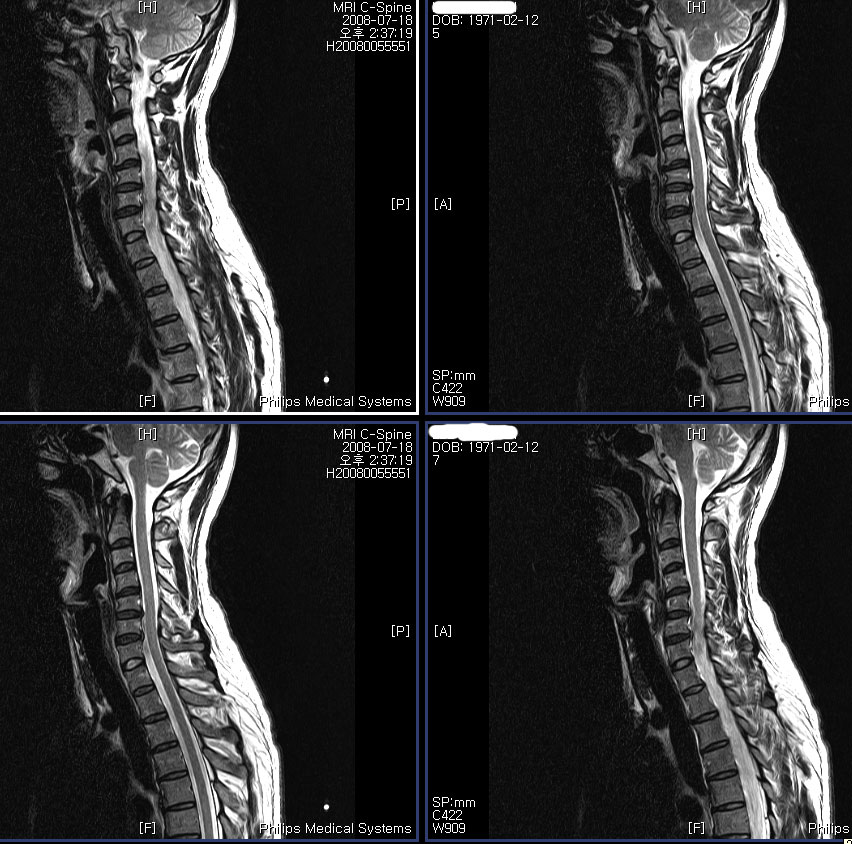

:,κ , Ʒκ(,ո) ٸ Ʒκ() ȭ- ȭ ǻ 콺 ۾ϱⰡ . 2008 5 Ȱ ٸ ȭ ִٰ 6뿣 ʿ Խϴ. MRIԿ 3 ġ Űֻ,ġ (ġ 1Ͽ1~2 ٰ ֱ ūǻ缱 ø ҽϴ) Űֻ縦 ̷ մϴ. ʹ ͳݰ˻ϴ ǥغ ˰ԵǾ Ϸմϴ. ̷ ڰ մϴ. ༺̶ ϼ̴µ ǻ缱Բ ģ ѻԴϴ. ڷ MRI纻 ֽϴ.Ϸ 帮ڽϴ. ------------------Ͽ Ͻ Ŀ ۼϽ ı--------------------- ũ, ֽϴ no 3366 date 2008-10-06 20:26:41 hits 329 name ع (gaeul72@nate.com) IP: 220.83.43.174 3 ,ٸ , ϴ MRI Կ ༺ ũ Դϴ. ġ ġ ұϰ ٸ ȣ ͳ ˻ ϴ ǥغ ˰ Ǿϴ. ʹ ˾ƺ ᱹ ġ ϳ ߽ϴ. 12ð Ѿ ư ʹ ҽϴ. 켱 ù ϰ ҽϴ. ſ ũ پٰų ϴ° ߽ϴ. Ѱ ε 谳 ΰ Ѱ Ʊٴ ǰұ ߽ϴ. 3 ȣǴ Ȯ Խϴ. ġ ϸ鼭 迣 ߰ Ծ ߴµ ʾƵ ŭ ϴ. ġ ġᵵ ް ǥغ㼱Բ ˷ֽ ϰ е带 ٲ㰡 õ ߽ϴ. α ȿ ٵ ϰ ʹٰ մϴ. ϰ ʹ ٸ Ⱑ ϴ. ̾ µ ٵ ʹ ϰ ٰ ߽ϴ. Ƴ ϳ ϰ ʹٰ մϴ. ó Ͻô е鲲 õϰ ͽϴ. [] http://3wboard.zicoree.com/New_Board/Board/Read.php?Page=1&dummy=1227866694&Board=compill-50-free1&No=3366&Search=Name&keyword=ع&period=1000 |